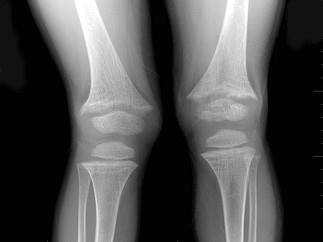

问题 男,6岁,睡眠差、夜惊、多汗、出牙较迟、血清磷减低、血清钙减低、碱性磷酸酶升高,结合图像,最可能诊断是?(?)

选项 A.维生素D缺乏病 B.骨质软化症 C.先天性骨梅毒 D.肾性维生素D缺乏病 E.脆骨病

答案 A